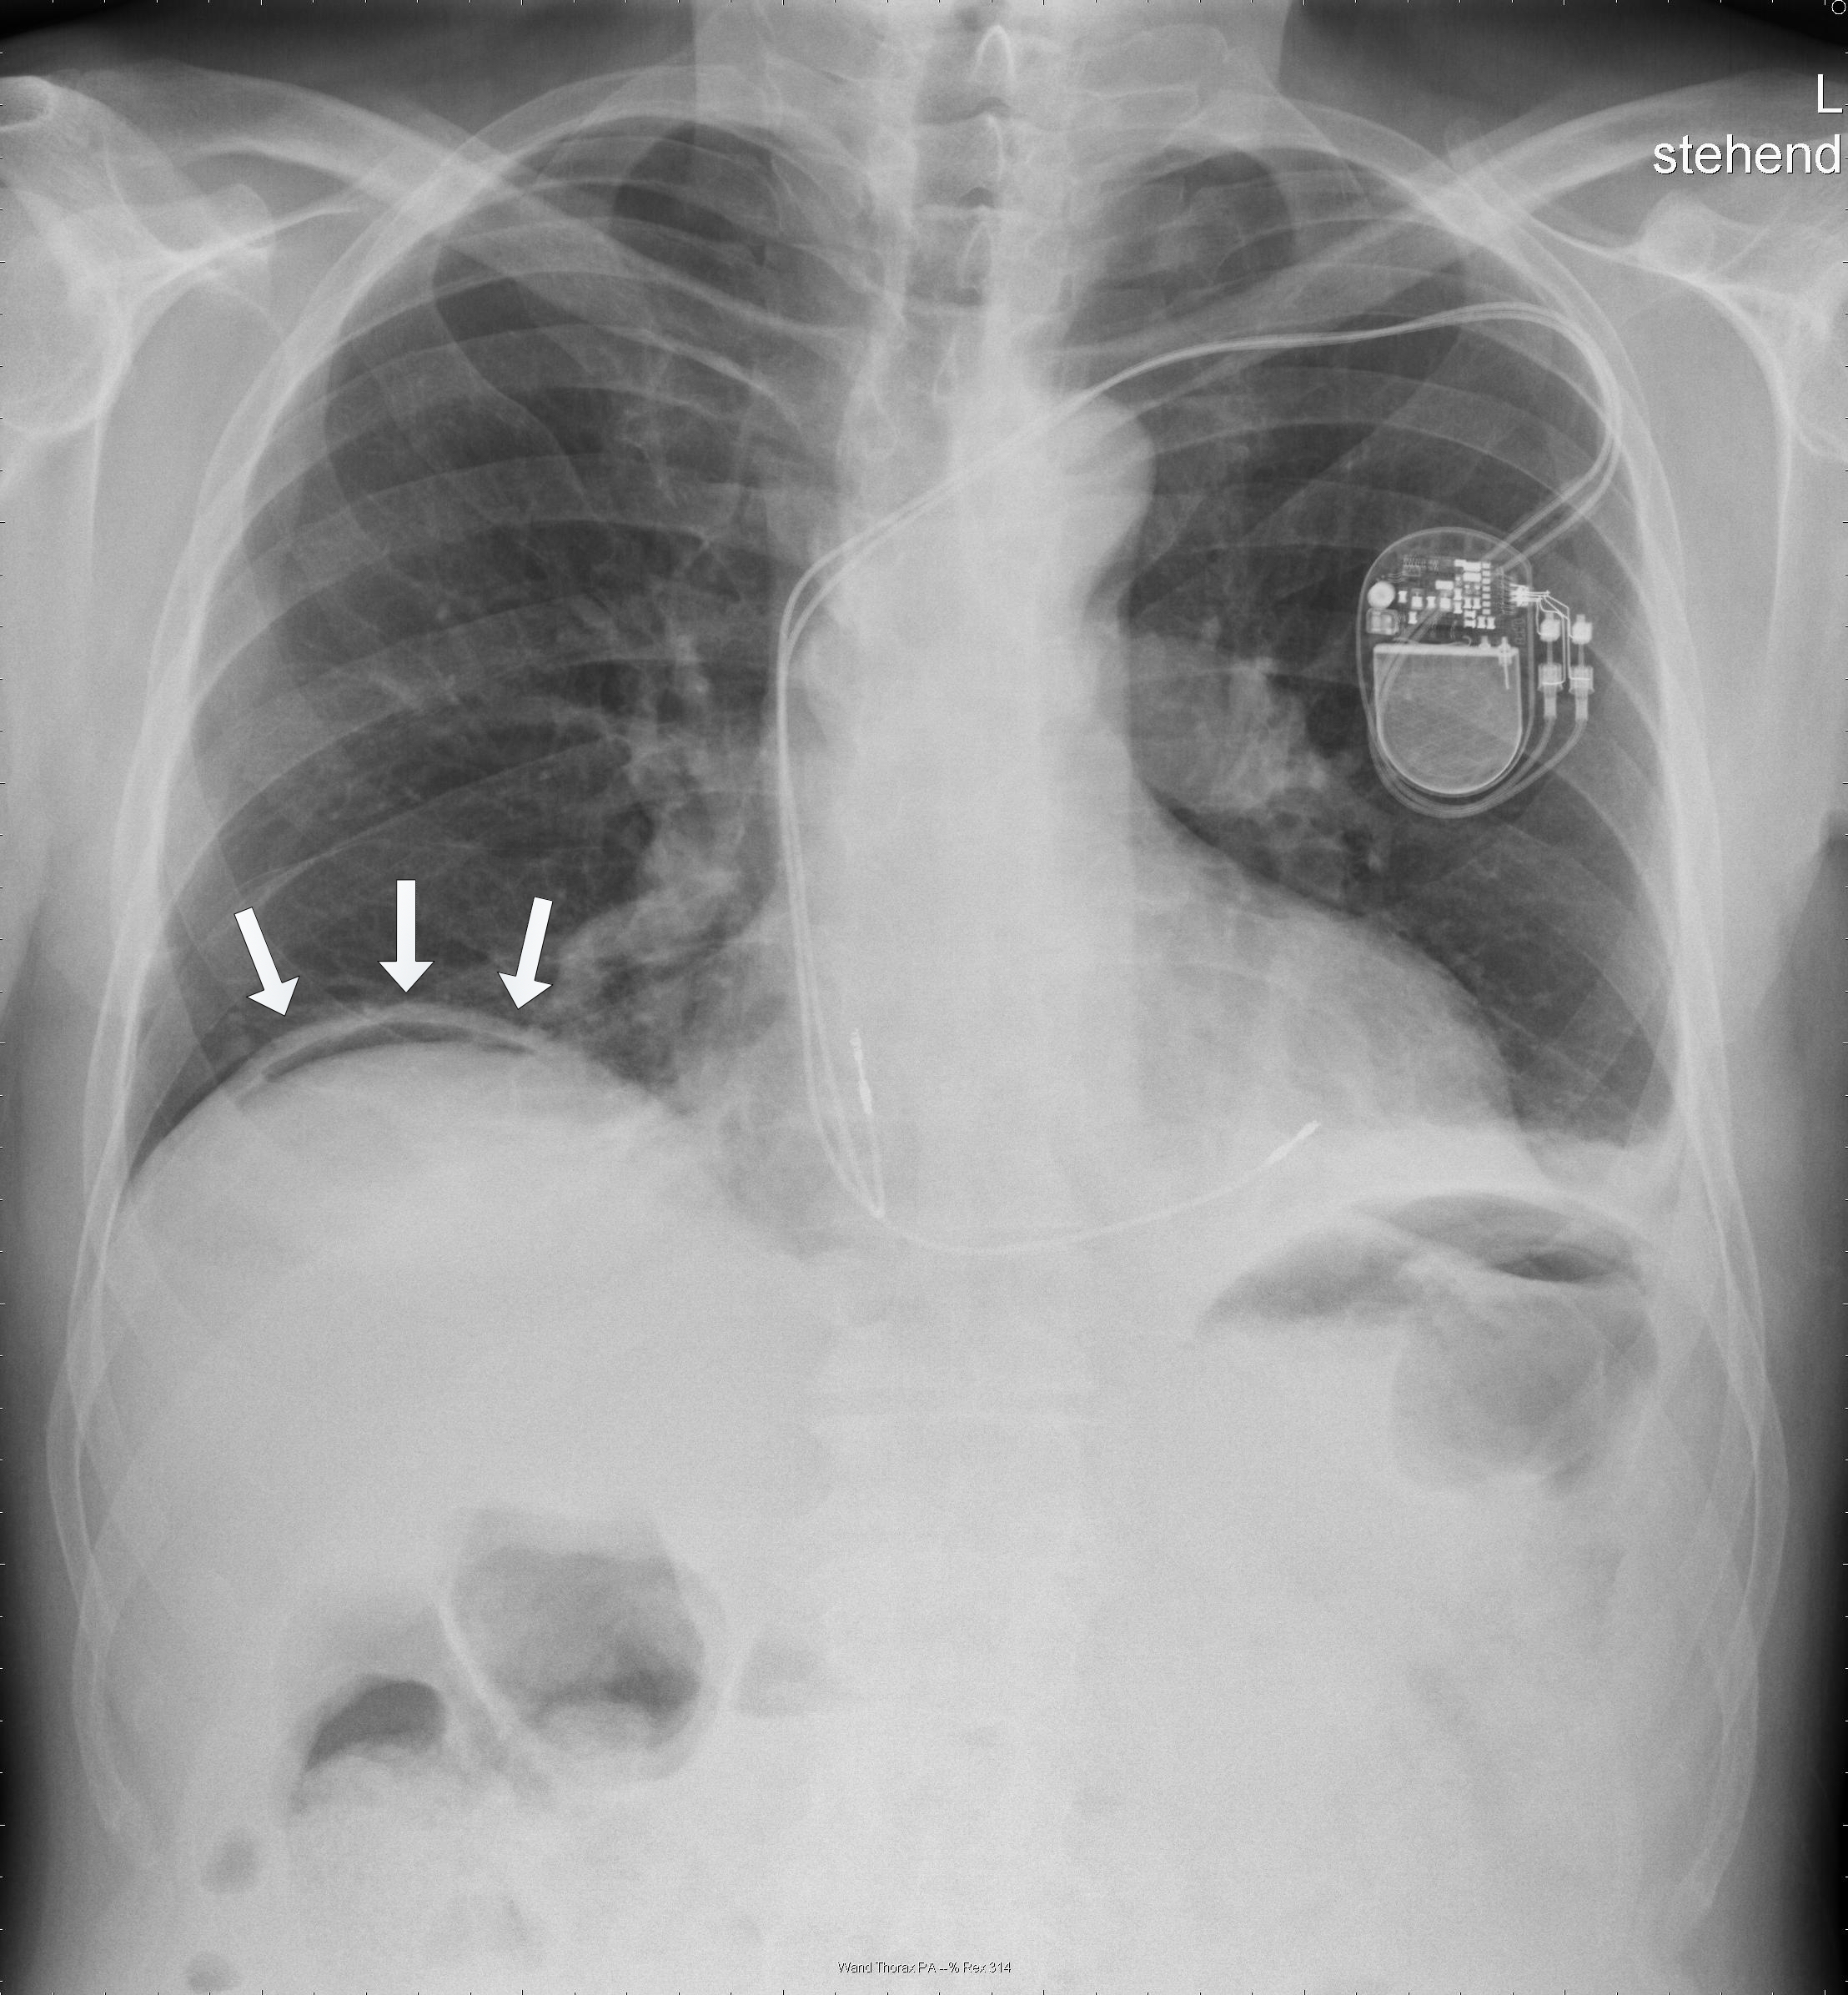

A physically fit 74-year old male with a known history of a left-sided inguinal hernia presented to our emergency department with lower abdominal pain after a fall while playing tennis. After striking the ball the patient fell forward, landed on both his hands and suffered a blunt trauma to his abdomen. He identified a swelling in the left groin and reduced the content back into the abdomen. Due to persisting pain in the lower abdomen he presented to our emergency department. The vital signs were normal and the examination showed tenderness in the lower abdomen without signs of peritonitis. No evidence of incarceration of the inguinal hernia was present. The white blood cell (WBC) count was 13’000 and the c-reactive protein was 17mg/l. The abdominal sonography showed no free fluid or air and the patient was hospitalized for analgesic treatment. Thereby the patient was free of symptoms on the following day. On the second day after the injury the condition of the patient worsened with vomiting and a ballooned abdomen. An erect x-ray of the chest showed free intraabdominal air (Figure 1). The labs showed a WBC count of 6’000, a c-reactive protein of 463mg/l, a creatinine of 136umol/l and normal liver enzymes and lipase. The computed tomography (CT) of the chest and abdomen with intravenous contrast

showed considerable free fluid, free air and a thickened wall of the sigma with multiple diverticula imposing as a pseudotumor without signs of an acute inflammation (Figure 2). This rose the suspicion of a traumatic sigma perforation. The left inguinal canal was fluid-filled with free air present (Figure 3). Because of the absence of an intensive care unit the patient was transported to a tertiary referral hospital for an urgent explorative laparotomy. The inspection showed a feculent 4-quadrant peritonitis with a perforation of the small bowel 50cm proximal to the ileocecal valve. The perforated small bowel was resected as a segment. A side-to-side ileostomy was formed. The sigma was indurated on palpation and suspicious of a colon cancer. In the intraoperative rectoscopy the tumor could not be reached. The inguinal canal was filled with stool and a lavage was performed together with the whole abdomen. A drainage was placed and the abdomen closed temporary with a negative-wound-pressure therapy (NWPT) system. The preoperatively started intravenous antibiotic treatment with imipenem was continued. On the first postoperative day, a rectosigmoidoscopy was unable to pass the stenosis in the sigma. A repeat CT of the abdomen with rectal and intravenous contrast showed wall thickening of the sigma with perifocal lymphadenopathy (Figure 4). In the 2nd look laparotomy 48 hours after the initial operation an anterior resection with complete mesocolic excision and partial mesorectal excision was performed because a malignant disease could not be excluded. A descendorectostomy was performed and the side-to-side ileostomy was reversed into a protective splitstoma. Again, the inguinal hernia was not touched due to the contamination. The NWPT was continued and after two NWPT changes primary fascial closure was achieved eleven days later. The histopathology showed a covered perforation of a sigma diverticulitis with inflamed pseudotumor without signs of malignancy. 22 days after the tennis accident the patient was discharged for rehabilitation. One month later he is in a good health condition and is waiting for the reversal of the stoma and definitive treatment of the inguinal hernia.